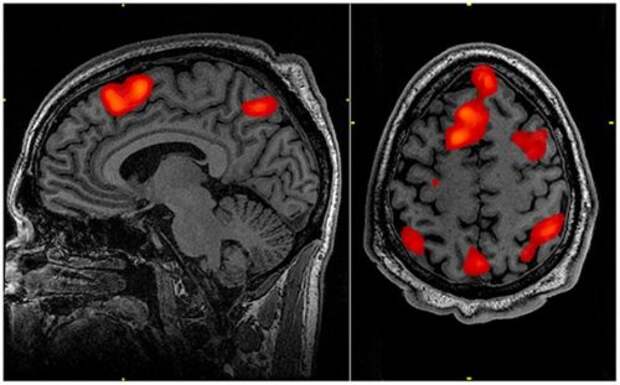

22. Влияние гипноза на наш мозг

В ходе изучения реакций коры головного мозга было доказано, что под гипнозом мы на самом деле переходим в альтернативное нейропсихологическое состояние.

22. Влияние гипноза на наш мозг

В ходе изучения реакций коры головного мозга было доказано, что под гипнозом мы на самом деле переходим в альтернативное нейропсихологическое состояние.